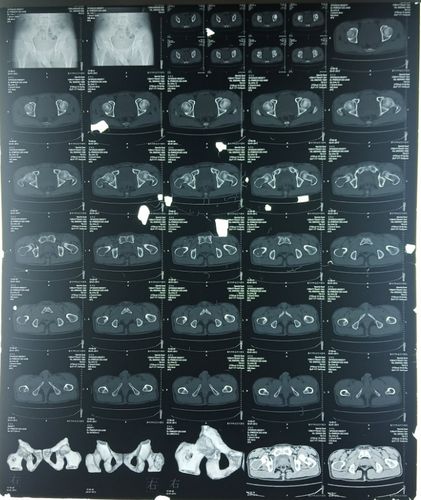

骨盆ct平扫图片解剖图

骨盆ct平扫图片解剖图,骨盆ct断层解剖图

【病例讨论】骨盆骨折是否手术

术前ct检查

术前ct平扫

骨盆,股骨头平扫

骨盆ct断层解剖图

正常骨盆ct平扫图片

骨盆ct断层解剖图骨窗

骨盆CT解剖